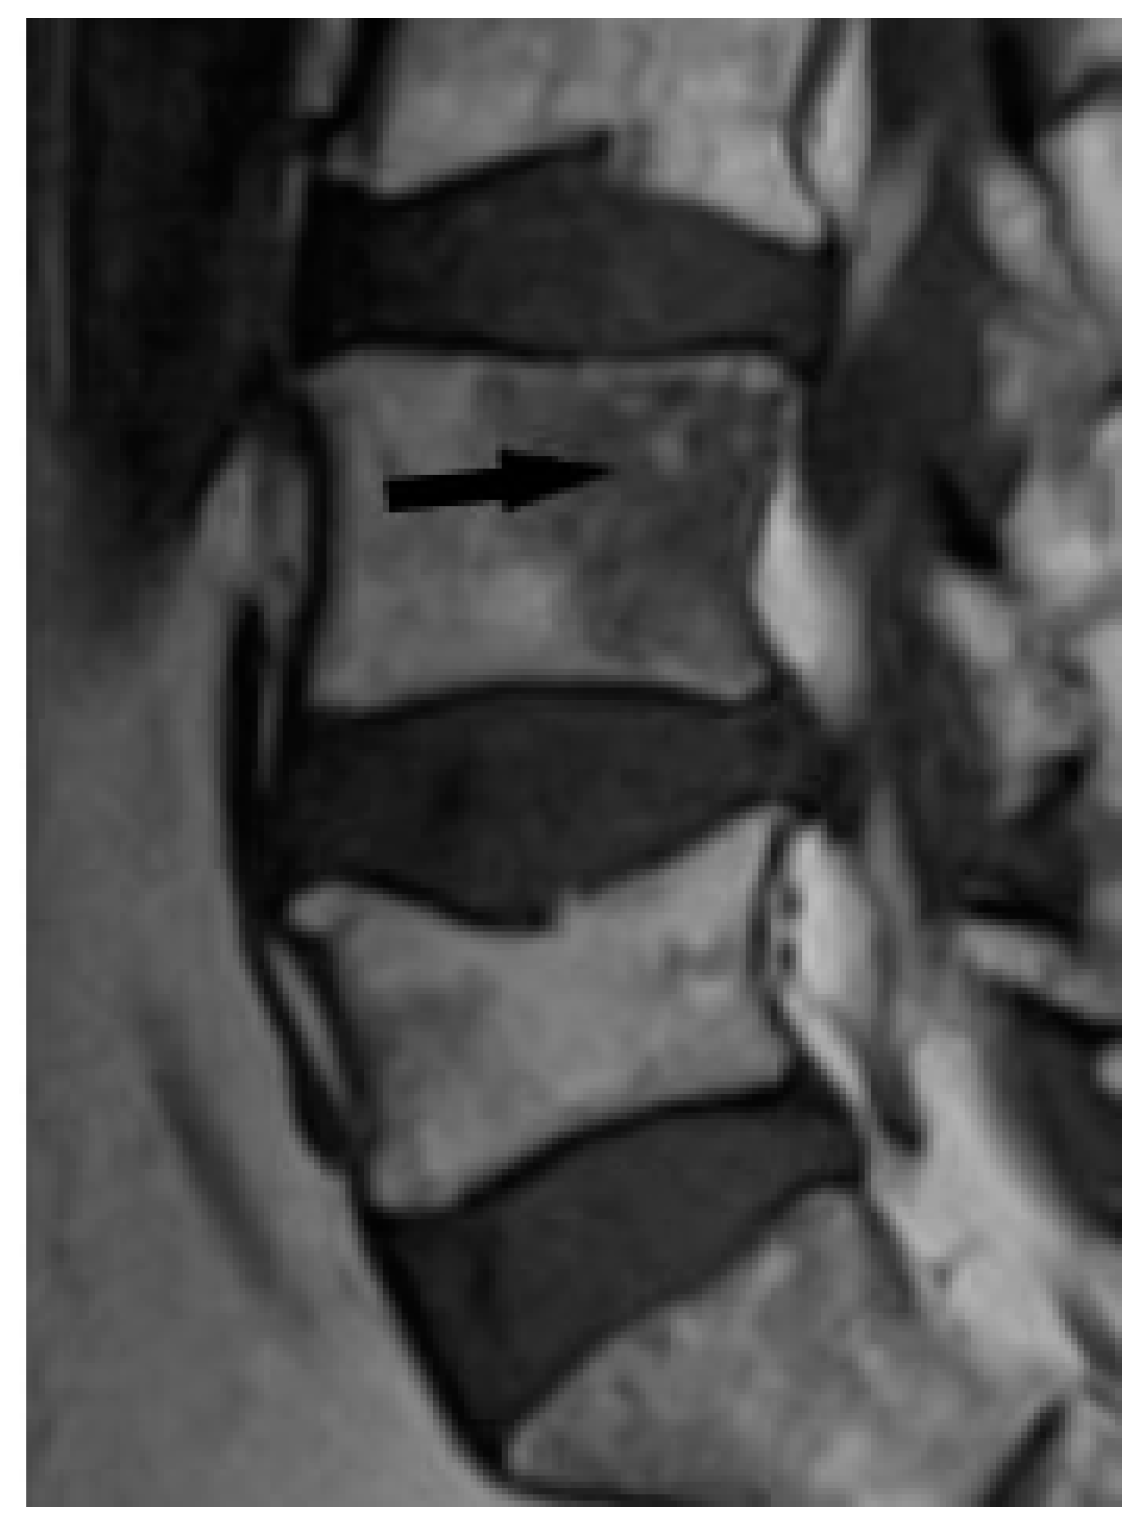

Bone marrow sarcoid foci are hypointense on T1-weighted images and hyperintense on T2-weighted and STIR image, with the same appearance as metastases, multiple myeloma or lymphoma [19] (Figure 8a,b). In T2-weighted images, lesions in sarcoidosis of the bone marrow may also show low and intermediate signal intensity, with signal being higher in STIR images [15].

The outlines of the lesions can be smooth or irregular, and sometimes the presence of normal fatty bone marrow within the lesion can be seen, which was thought to be an indicator of the benign nature of the lesion [15] (Figure 9). The presence of fat in the lesion may indicate involution. An additional differentiating feature may be the presence of a mass in the soft tissues, which is extremely rare in sarcoidosis, but more common in metastases [15].

Figure 9. T1-weighted image. Hypointense lesion with irregular margins and with small foci of hyperintense fat (black arrow).